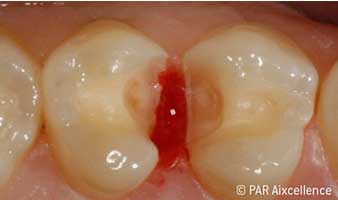

Abb 5: Nach weiterer Exkavation weiterhin klinisch deutlich sichtbare Karies, approximal Fissur scheint kariesfrei zu sein.

Abb 6: Bild wie Abbildung 5 - diesmal unter Anwendung von Facelight: Karies jetzt auch deutlich in den Fissuren erkennbar.